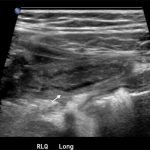

In the long axis video, the appendix appears as an enlarged, non-compressible, blind-ending tubular structure (white arrow) with distinct appendiceal wall layers and lack of peristalsis. In the short axis video, the appendix appears as a target sign (yellow arrow) between the abdominal and psoas muscles. The maximal outer diameter (MOD) measures 11.8mm and the appendix wall measures 0.17mm. There is trace adjacent free fluid and echogenic periappendiceal fat. Transverse axis video and image (red arrow) demonstrate that the appendix is not compressible. These findings are consistent with acute appendicitis.